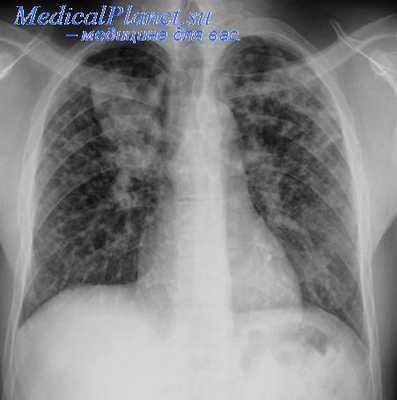

Мы считаем ранние сращения более легко пережигаемыми. Повышенная ваекуляризация сращений и их особая рыхлость наблюдались нами у 14% больных. Операции при ранних торакокаустиках, как мы видели из нашей статистики, не более опасны в смысле кровотечений, чем при поздних.

Неточность и произвольность понятия «ранняя» и «поздняя» торакокаустика с теоретической точки зрения доказываются на нашем материале тем, что у нас было 17 больных, у которых с момента выявления заболевания до наложения искусственного пневмоторакса прошло от 1 года до 10 лет.

Осложнений, которые могли бы быть связаны с близостью легочной ткани в коротких сращениях в плевре (ранение легкого, перфорация его, гнойные эмпиемы и т. п.), у наших больных не наблюдалось, что доказывает неосновательность доводов сторонников поздних торакокаустик и в данном вопросе.

Мы являемся сторонниками своевременного наложения искусственного пневмоторакса и возможно более быстрого исправления неэффективных пневмотораксов с учетом индивидуальных и клинических особенностей, показаний и противопоказаний к операции у каждого больного.

Выводы:

1. Раннее пережигание сращений не представляет большой опасности в отношении кровотечения, повреждения легочной ткани и увеличения плевральных осложнений.

2. Срок применения торакокаустики связан с возможностью безопасного введения инструментов в плевральную полость и манипуляций ими при операции.

3. При отсутствии видимых сращений и при наличии каверны необходим некоторый срок для выявления эффективности искусственного пневмоторакса.

4. Всякое сращение, определяемое рентгенологически, является поводом для торакоскопии при отсутствии протвопоказаний к оперативному вмешательству со стороны общего состояния больного, состояния второго легкого, плевральной полости и функции диафрагмы на противоположной стороне.

5. При отсутствии противопоказаний торакоскопия должна применяться тогда, когда создан достаточный газовый пузырь и необходимое нулевое или близкое к нему давление.

6. Врач не должен быть связан искусственно созданными понятиями о «ранней» и «поздней» торакокаустике и широко применять ее, исходя из индивидуальных показаний у каждого больного.